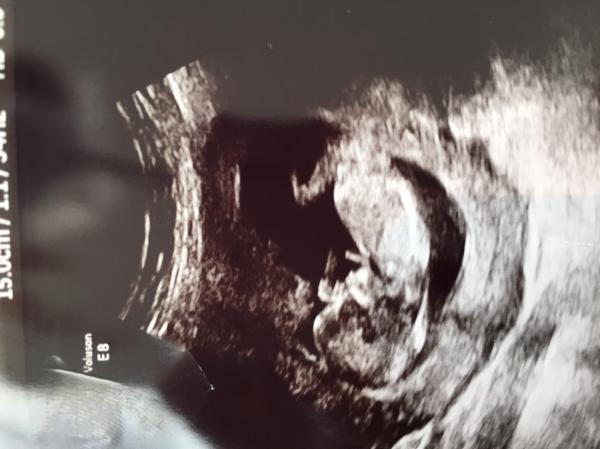

Kub klar. Så skönt att få se den lilla skutta omkring där inne. ????

Berättade för barnen igår. Visade UL bilden från kub. Dem blev såklart superglada.